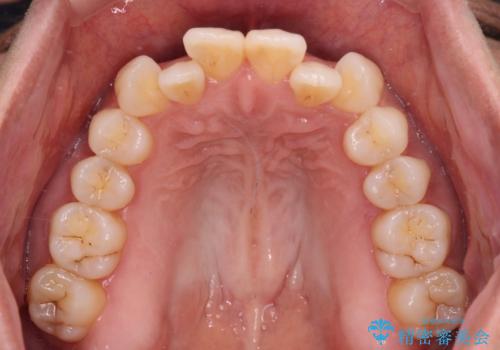

- 上下のクロスバイトと前歯のデコボコを気にして来院された患者様です。

インビザラインを用い、IPR(歯と歯の間を削る)と歯列全体を拡大させることで、歯並びを整えていくこととしました。